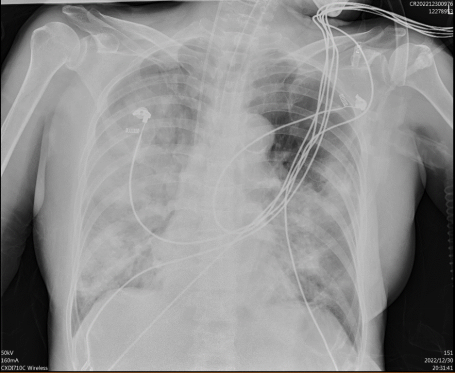

2022-12-30胸片:考虑双肺广泛渗出,主动脉粥样硬化

2023-2-8胸部CT:(见图1、图2)

• 考虑双肺感染,多发脓肿及空洞形成,支气管扩张。

• 对比2023-01-30胸部CT,部分空洞较前稍缩小,余大致同前

2023-2-12胸片